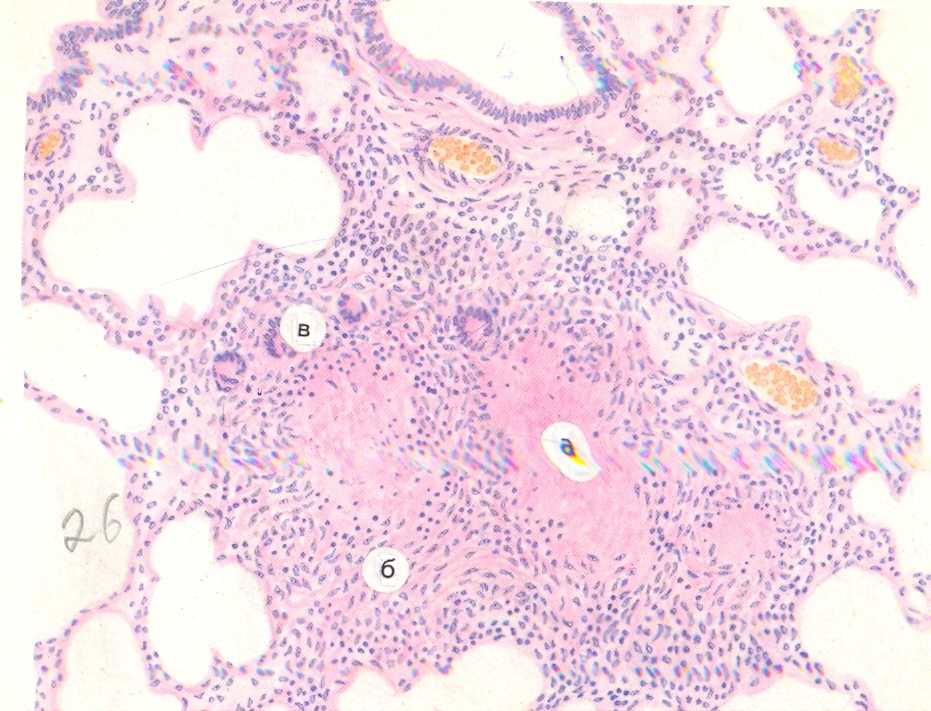

Карнификация Легкого: Микропрепараты и Диагностика

Раздел: Калейдоскоп образов